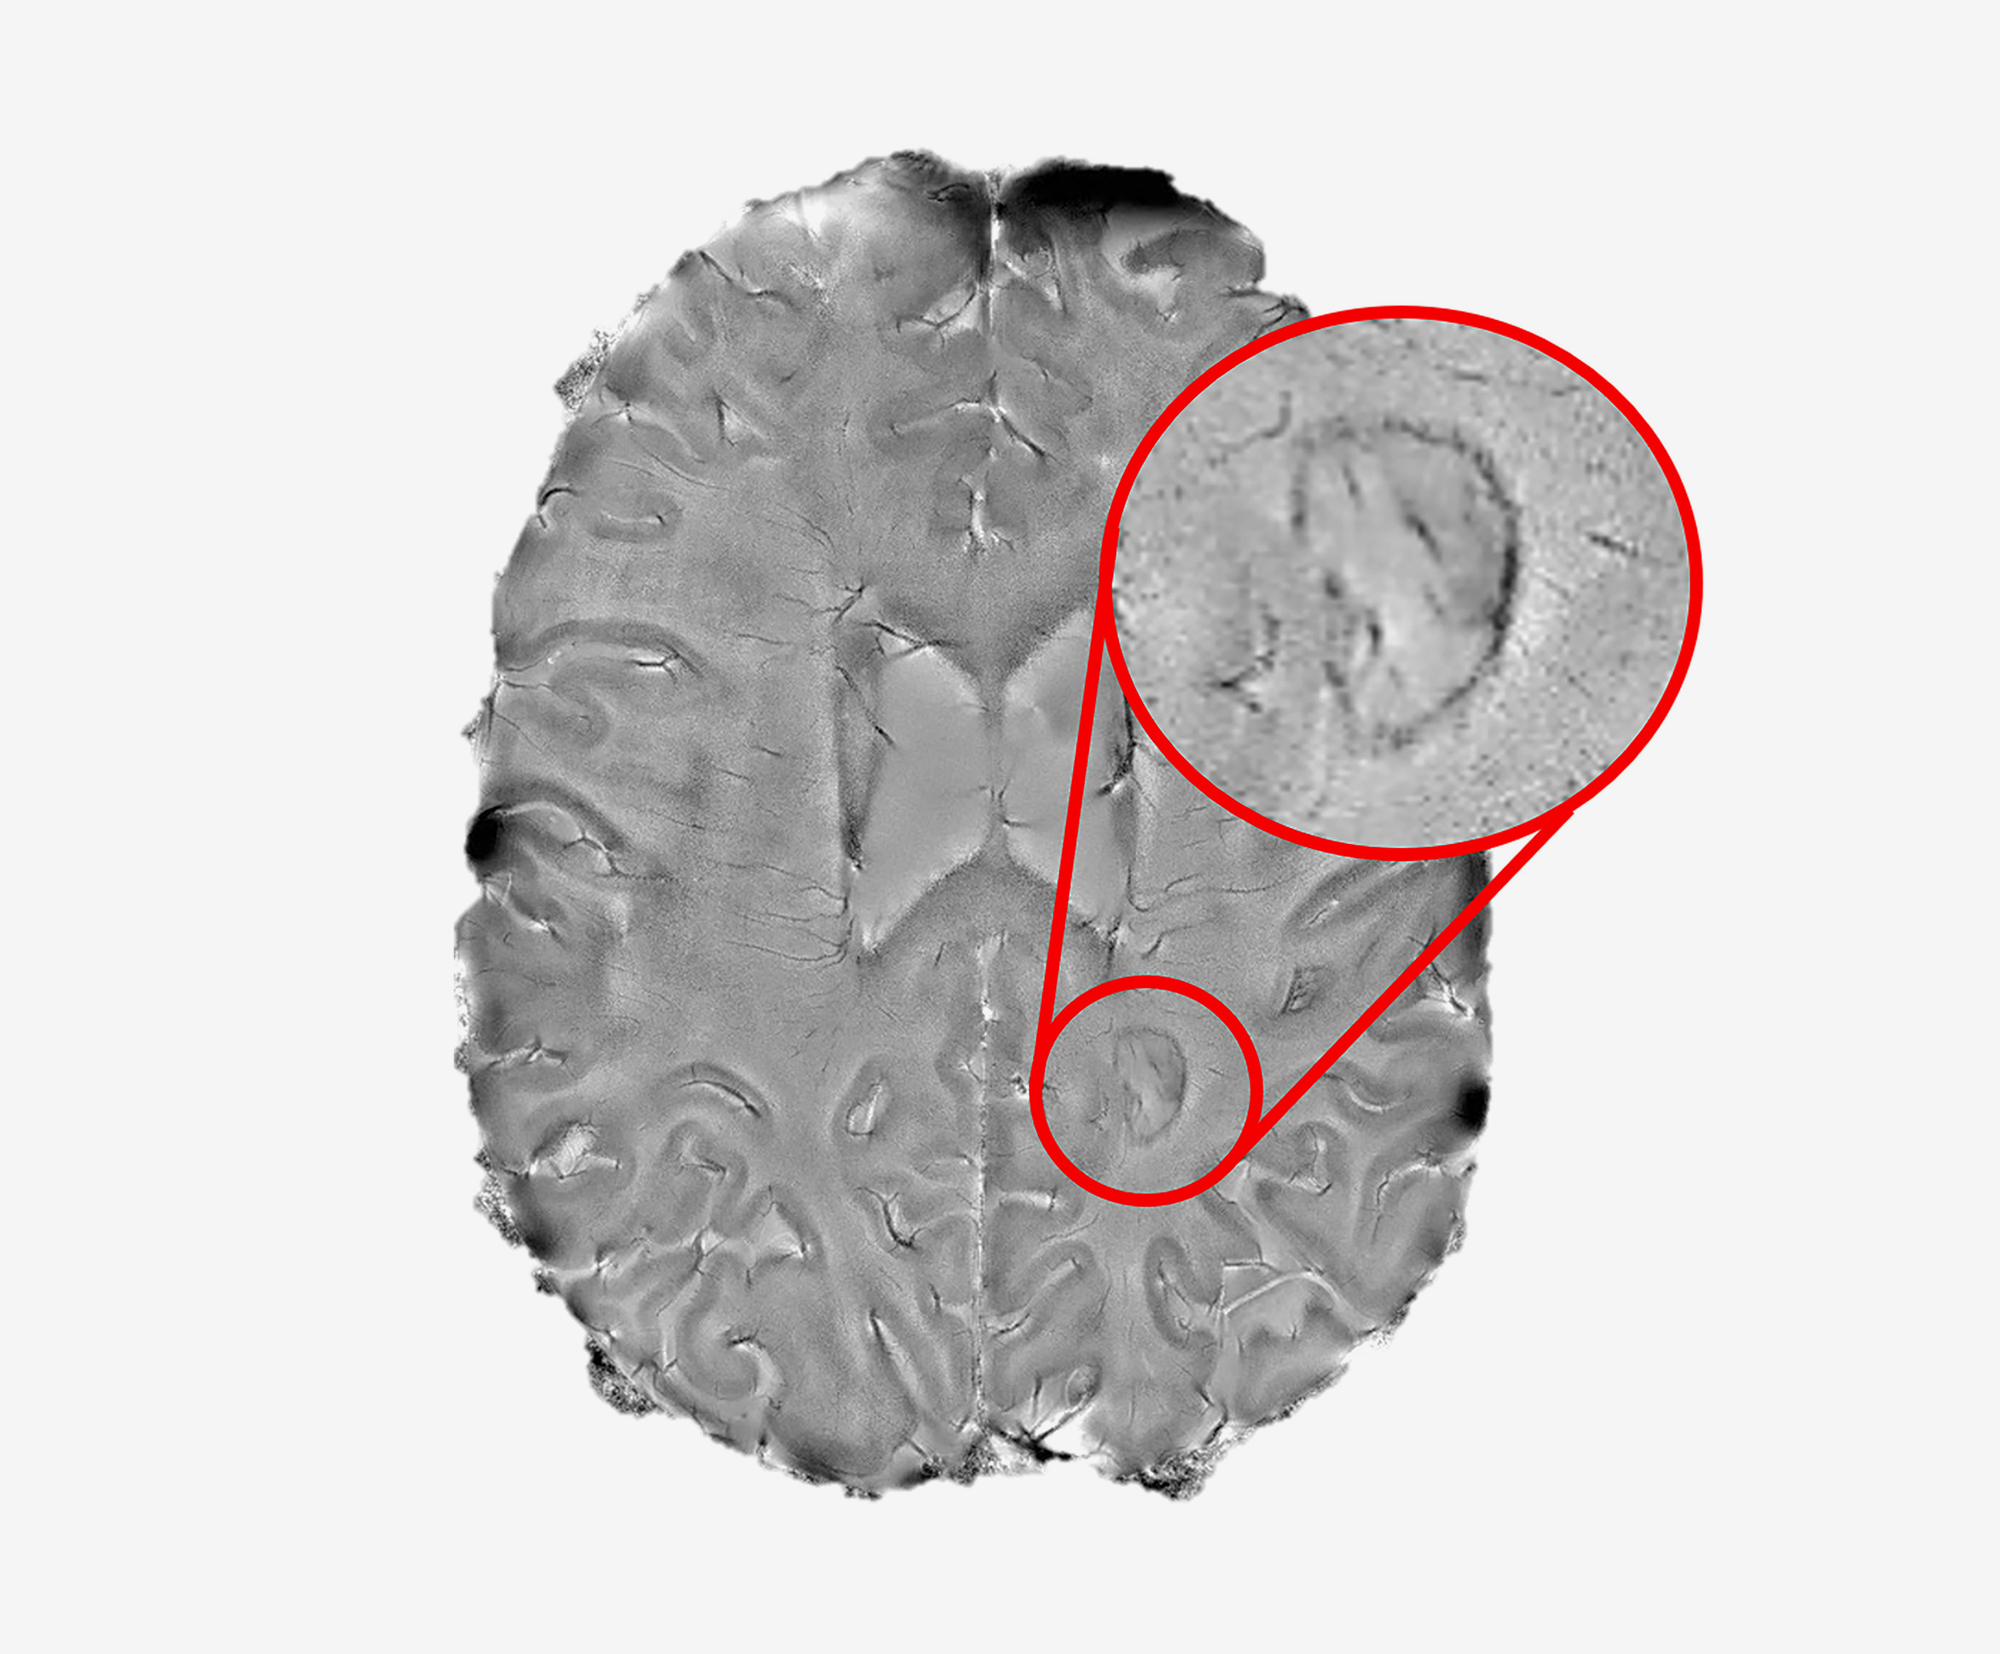

Doctors often use magnetic resonance imaging (MRI) to diagnose patients as the immune system’s attack produces lesions that appear as spots on scans of patients’ brains. While some of the lesions heal, completely or partially, other lesions remain and rimmed ones appear to actively expand, or “smolder”, for many years. Nevertheless, until recently, researchers did not fully understand the role chronic active lesions play in the disease, in part, because it was difficult to find the ones that remain chronically inflamed.

Starting in 2013, Dr. Reich’s team showed that by using a high-powered, 7-tesla MRI scanner, they could accurately identify damaging, chronic active lesions by their darkened outer rims, in agreement with previous studies.

Finally, the team used a 3D printer to compare the spots they had seen on scans to the lesions they observed in brain tissue samples autopsied from a patient who had passed away during the trial. They found that all expanding rimmed spots seen on the scans had the telltale features of chronic active lesions when examined under a microscope.